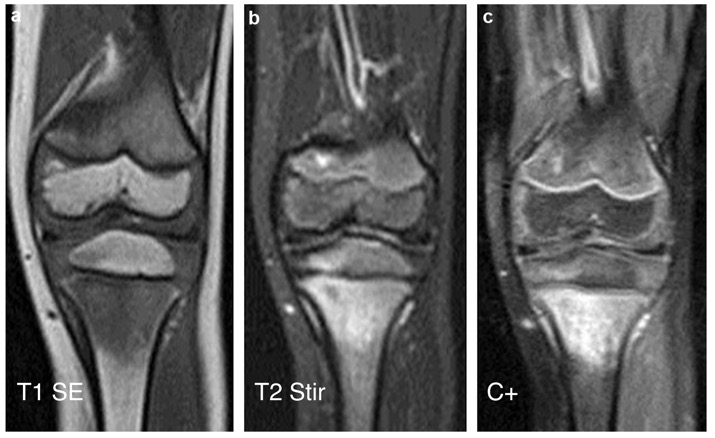

IRM

œdème médullaire (STIR ou T2 FatSat, STIR permet grand champs coronal) / envahissement du CC et chondro-épiphyse?

T1 SE pour conversion médullaire

=> hyposignal T1 et hypersignal T2 et STIR à limites floues, punctiformes (gouttelettes graisseuses)

T1 C+: pour la caractérisation tissulaire, abcès (médullaire, sous-périosté ou tissus mous) = C+ périphérique